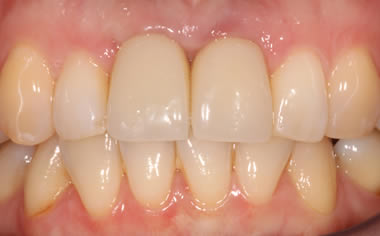

More front teeth replaced by dental implants

Case Three (4 images)